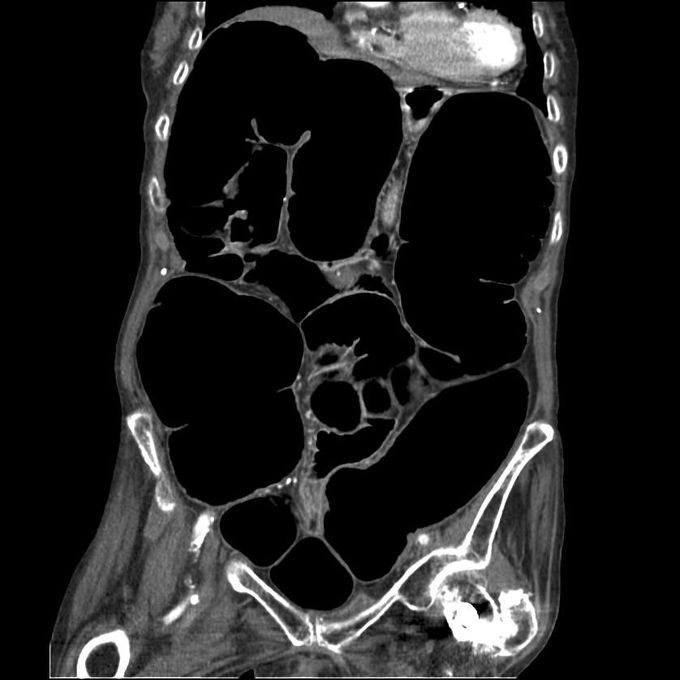

Ogilvie's syndrome is an example of adynamic bowel obstruction. It is one of the causes of pseudo-obstruction of the colon resulting in dilatation of proximal part in an acute setting. Typically, no mechanical cause of the obstruction is found. Reference: https://www.uptodate.com/contents/acute-colonic-pseudo-obstruction-ogilvies-syndrome#:~:text=and%20diagnosis%22.)- Image via: https://en.wikipedia.org/wiki/Ogilvie_syndrome